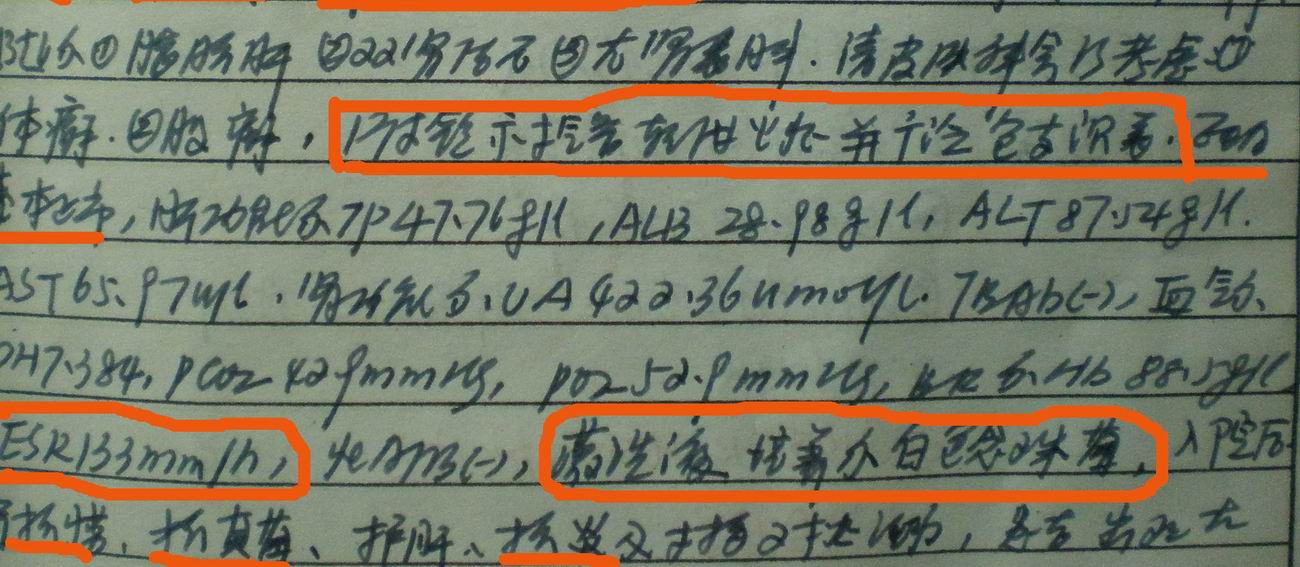

病人资料:男,52岁,因体癣股癣等皮肤病行激素治疗,因突然大剂量减药而起病,病情危急,9月8日曾在上级医院住院治疗,9月18日复查了ct片,相关检查及住院小结以图片资料上传。

上级医院住院小结:

[face=宋体]显然上级医院进行了抗结核,抗真菌,抗炎等治疗,目前病人肺内病灶基本消失,双侧胸腔积液,右侧积液量有吸收,抗结核一个多月,现在病人疑问,结核的诊断是否有疑义,抗结核是否继续,因为那个毕竟副作用大。[/face]

我仔细看了下病人的出院小结,当时情况危急,诊断里有1型呼衰。心包周围的是脂肪密度。结合三次ct扫描的图象分析,个人认为:1、病人目前肺部病灶基本消失,双侧胸腔内少量积液,抗结核治疗才一个多月,就算是结核,抗结核治疗有效果,为何效果如此好,一点纤维灶的痕迹都没有呢,再就是患者做过气管镜检查及活检、痰检均未找到结核的证据。所以不支持结核的诊断。